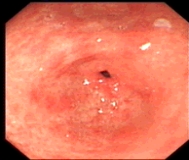

内镜下表现:黏膜红白相间,以白色为主,黏膜皱襞变平或消失,部分黏膜血管显露,可伴有黏膜颗粒或结节状等表现。如伴有肠化生于电子染色窄带成像放大内镜(NBI ME)下发现胃粘膜上皮细胞表面的脑回样结构嵴部的纤细浅蓝色线样结构。病理活检可进一步确诊。

萎缩胃表现